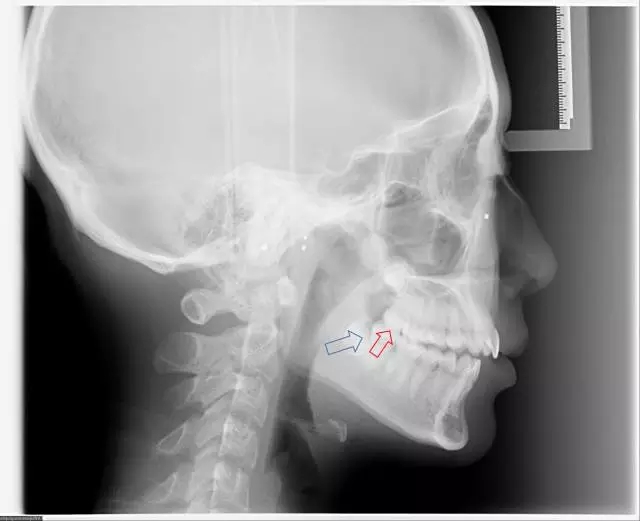

完全埋在牙槽骨里的下頜智齒,它本身倒是不出問題。但是這些近中或水平阻生的智齒,會推擠下頜第二磨牙,導致第二磨牙伸長:

0.gif

然后,第二磨牙造成咬合干擾、早接觸,前牙開 牙合…………

甚至髁突吸收: